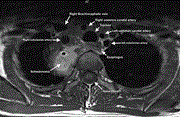

Central venous catheter placement leading to an emergent paramedian sternotomy: a case report

Keaton Cooley-Rieders and others

Journal of Surgical Case Reports, Volume 2020, Issue 9, September 2020, rjaa368, https://doi.org/10.1093/jscr/rjaa368